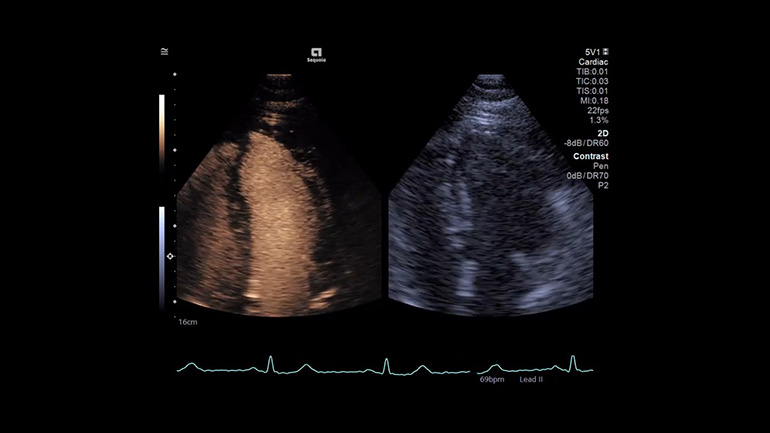

УЗИ с контрастным усилением (CEUS)

Мощная архитектура УЗ-системы ACUSON Sequoia обеспечивает визуализацию контрастного препарата на больших глубинах и с большей четкостью, чем когда-либо ранее.

Технология импульсных последовательностей для режима контрастирования (CPS) Технология импульсных последовательностей контрастирования обеспечивает подавление артефактов яркости при движении потока крови и превосходное подавление сигнала от смещающихся тканей, участвующих в акте дыхания. Благодаря своей высокой специфичности и чувствительности технология CPS позволяет получать изображения на большей глубине у тех пациентов, для которых ранее контрастные исследования затруднены.

​Контрастная гармоническая визуализация (CHI) Режим контрастной гармонической визуализации обеспечивает высокое разрешение и высокую частоту кадров с одновременным сохранением долговечности микропузырьков (по сравнению с CPS) контрастного препарата. Режим CHI — отличный инструмент для визуализации кровоснабжения поверхностных структур, который при необходимости обеспечивает и превосходную глубину проникновения ЭХО-сигнала.